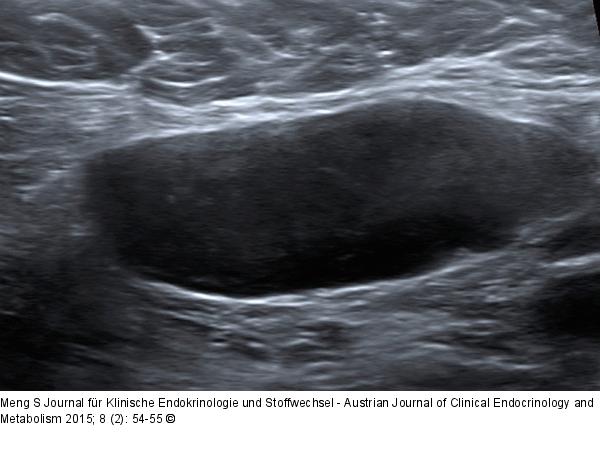

Abbildung 2: Ultraschall-Lymphknoten Fehlender Hilus. Dieser Lymphknoten weist keinen Hilus auf, alle anderen Kriterien sind jedoch erfüllt. Tumorzellen destruieren die reguläre Architektur des Lymphknotens und führen so zu einer Obliteration der Hilusstruktur. „Diffuse large B-cell lymphoma“ (DLBCL). |